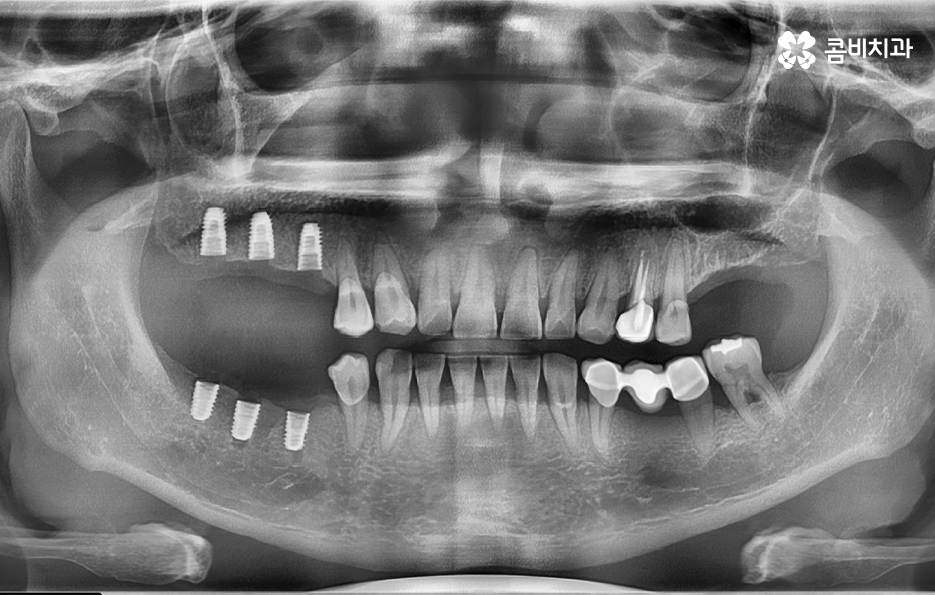

40대임플란트 치료에 대해 알아보신다면 우선 치아를 상실한 원인에 따라서 치료 방법이 다소 차이가 날 수 있는데요. 대표적으로 충치가 심해져서 발치를 하게 된 사례와 치주염으로 인해 잇몸이 약해져서 발치하게 된 사례로 구분해 본다면 충치 만으로 치아를 발치한 경우 잇몸 상태가 양호할 때 원데이임플란트로도 치료가 진행되거나 무난하게는 일반적인 임플란트 치료 과정으로 진행될 수 있어요

반면에 치주염이 심해져서 치조골이 녹아내리고 이미 치아의 뿌리가 보일 정도로 잇몸이 약해진 상태에는 치아 발치 후 잇몸이 충분히 회복한 뒤 임플란트를 식립할 수 있는 잇몸 뼈가 충분한지 확인 후 경우에 따라서는 뼈이식이 추가될 수 있는데요.

임플란트는 잇몸 뼈에 식립하기 때문에 치주염으로 인해 잇몸 뼈가 부족하거나 치아를 발치 후 오랜 시간이 지난 다음에 임플란트를 하게 될 경우 임플란트를 식립할 충분한 잇몸 뼈의 확보를 위해 뼈이식을 받아야 할 수 있어요

쉽게 생각하면 임플란트는 인공치근으로도 불리고 있는데 치아의 뿌리를 대신하여 임플란트가 잇몸 뼈에 식립되고 골유착 과정을 통해 단단하게 고정되어 저작력을 얻고 있는데요

40대임플란트 치료에 있어도 잇몸 뼈가 중요하고 치료 후에도 잇몸 상태를 얼마나 건강하게 관리하냐에 따라서 치료도 원활하게 진행되고 치료 후에도 건강하게 수명을 유지할 수 있다고 볼 수 있는데요

생각보다 많은 40대 환자분들이 충치 외에도 치주염으로 인해 풍치 진단을 받고 치아를 발치하게 되는 사례가 많기 때문에 40대임플란트 치료 과정 중에 잇몸 뼈의 중요성에 대해 설명드려야만 왜 나는 치료 방법이 달라지고 뼈이식을 받아야 하는지 등과 같은 궁금증을 해소할 수 있을 거예요

물론 앞니가 사고로 부러지거나 어금니에 충치가 생겨서 발치하게 된 사례와 같은 경우에는 비교적 잇몸 상태는 양호한 경우도 많기 때문에 임플란트를 알아보시면 흔히 접하게 되는 원데이임플란트와 같은 치료 방법이 가능한 분들도 있을 거예요

하지만 앞서 설명드린 것처럼 30대 이후에는 치주질환을 앓게 되는 분들이 급격히 늘어나며 치주질환 관리가 잘 안되신 분들의 경우 40대에도 치주염으로 인해 치아를 상당수 잃게 되는 사례도 적지 않게 확인되고 있어요

40대임플란트 대상자분들의 경우 아직 젊은 나이이기 때문에 치료 자체는 큰 무리 없이 진행되는 경우가 많지만 임플란트의 수명을 고려한다면 향후 유지관리에 대한 부분을 잘 생각하고 치과 선택에 신중하실 필요가 있는데요